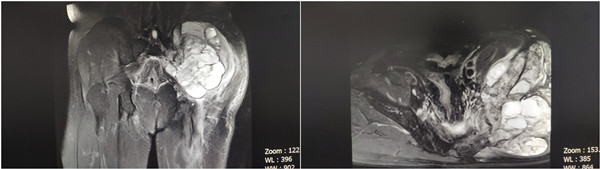

患者系51岁男性,八个月前不慎左臀部受伤,局部肿痛明显,以外伤于当地医院就诊后予对症治疗,但无明显改善并且症状加重,行臀部CT及磁共振检查,显示骨盆巨大软组织肿瘤,合并髂骨病理性骨折并向盆腔侵袭。患者于省内多家三甲医院就诊,行肿块穿刺活检,病理结果提示“高级别肉瘤,伴肌源性分化”。患者辗转来到我院骨三科,张纯教授团队复查CT及磁共振发现肿瘤包绕坐骨神经并与盆腔大血管关系密切,术中极易出现大出血及神经损伤导致严重并发症。

术前CT

全科对患者病情进行术前讨论并做好充分准备,术前行骨盆3D打印。院内多学科MDT会诊,肿瘤科、普外科分别给予专业建议,并在介入科行血管栓塞治疗。术中可见瘤体约25*15*10cm大小,侵蚀左侧髂骨约10*7cm,并向盆腔内呈梭形侵蚀约8*6cm,于坐骨大孔处包绕坐骨神经,结合术前3D打印,手术历时6小时,出血600ml,完整行肿瘤囊外切除,一并切除髂骨病灶,并予术中重建,术中全程电生理监测显示神经损伤未加重。